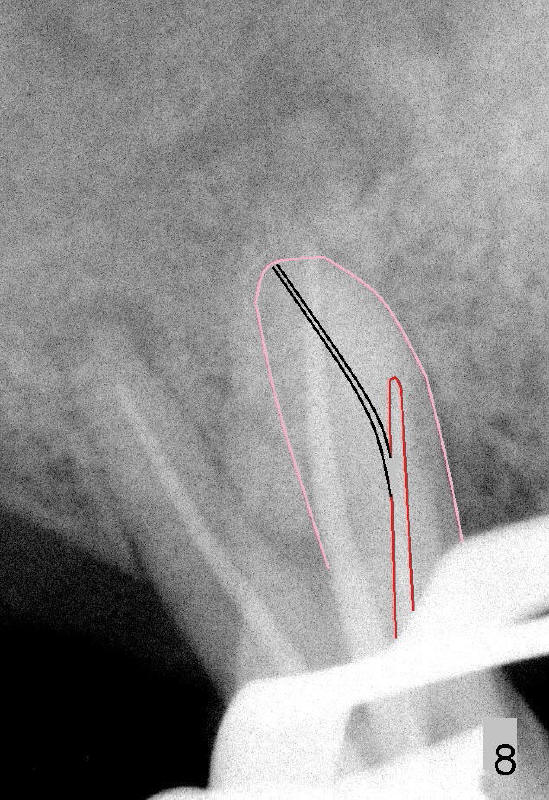

files达到不了工作长度(WL),但是衡量自己能力和时间,并没有进一步努力。时间还花在增加远中颊侧根和鄂侧根WL(其实没有必要,比较图四,图七),结果那里糊剂超充。副牙胶尖还充到原来ledge那里(图七箭头),如果第一次根管治疗就有CT指导,这样事情就有可能避免。图八显示根尖三分之一弯曲根管(黑线)与第一次根管扩大部分(红线)关系。